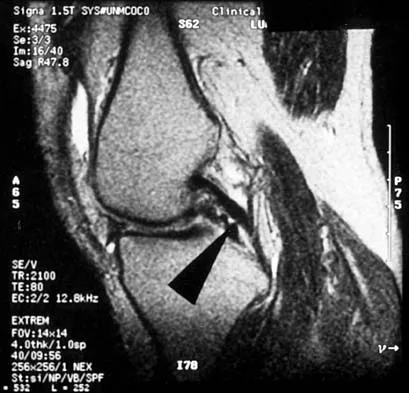

A 48-year-old man has recurrent right knee pain. Figure 52a shows the sagittal proton density T2-weighted MRI scan, and Figure 52b shows the sagittal T2-weighted MRI scan at the same level. The arrow is pointing to a